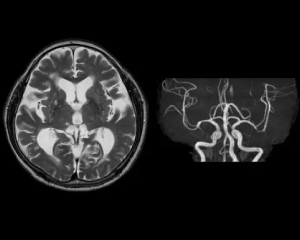

MRI検査室

当院では2023年11月より最新機種Philips社製1.5TMRI装置Ambitionを導入し運用を開始しました。従来装置に比べ撮像時間の短縮、画質向上また、新たな撮像方法による診断の質の向上が目的です。

装置の特徴

- ・最新のAIを搭載

- 画像ノイズを除去することにより画質が向上

撮像時間の短縮につながる例)頭部ルーチン検査(MRA含む)

従来装置 15~20分程度

最新装置 10~12分程度

- 頭部画像